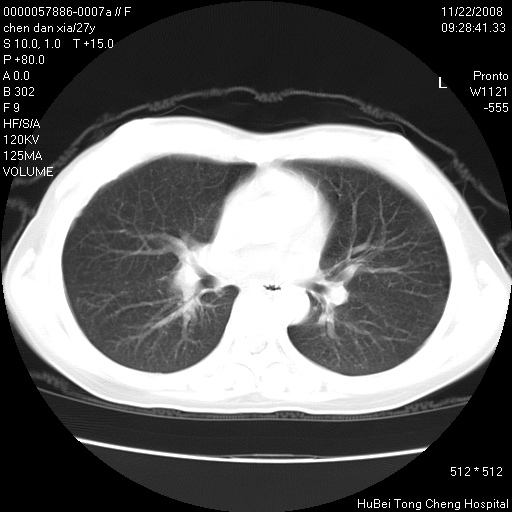

标题: CT16752:F,27Y。发热咳嗽20余天,伴盗汗。 [打印本页]

标题: CT16752:F,27Y。发热咳嗽20余天,伴盗汗。

考虑双肺粟粒性肺tb,右侧胸膜增厚.

气管前腔静脉后淋巴结肿大 右肺门纹理模糊

淋巴结核?

右下肺见片絮状影,两肺野内分布不均的小结节影,结核并肺内播散可能性大,建议结合实验室检查 .

右下肺纹理模糊;纵隔可见肿大淋巴节;右心缘旁结节,边缘光滑,纵隔窗病变范围较肺窗明显小,首先考虑右下肺结核,不排外淋巴瘤

双肺纹影普多,部分呈网状,支炎或淋巴管炎?

纵隔内淋结肿

局部胸膜增厚

下肺结节,结节内钙化,肺门纵隔淋巴肿大 结核可能性大

似有粟米状结节。考虑粟粒型肺结核?

1)考虑两肺感染性病变。2)纵隔淋巴结肿大。